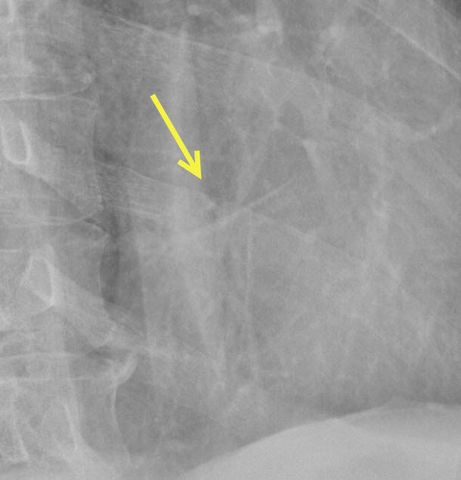

Any movement was painful, but this was exaggerated by the

When not out of alignment, rib fractures can be difficult to

find, but this one seems rather obvious.![]() |